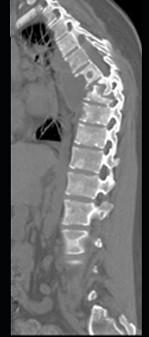

问题 男,34岁,发热,背部疼痛,不能直立,局部软组织肿胀,结合图像,最可能的诊断是 ( )

选项 A、骨肉瘤 B、成骨肉瘤 C、脊柱结核 D、脊柱转移瘤 E、化脓性骨髓炎

答案 E